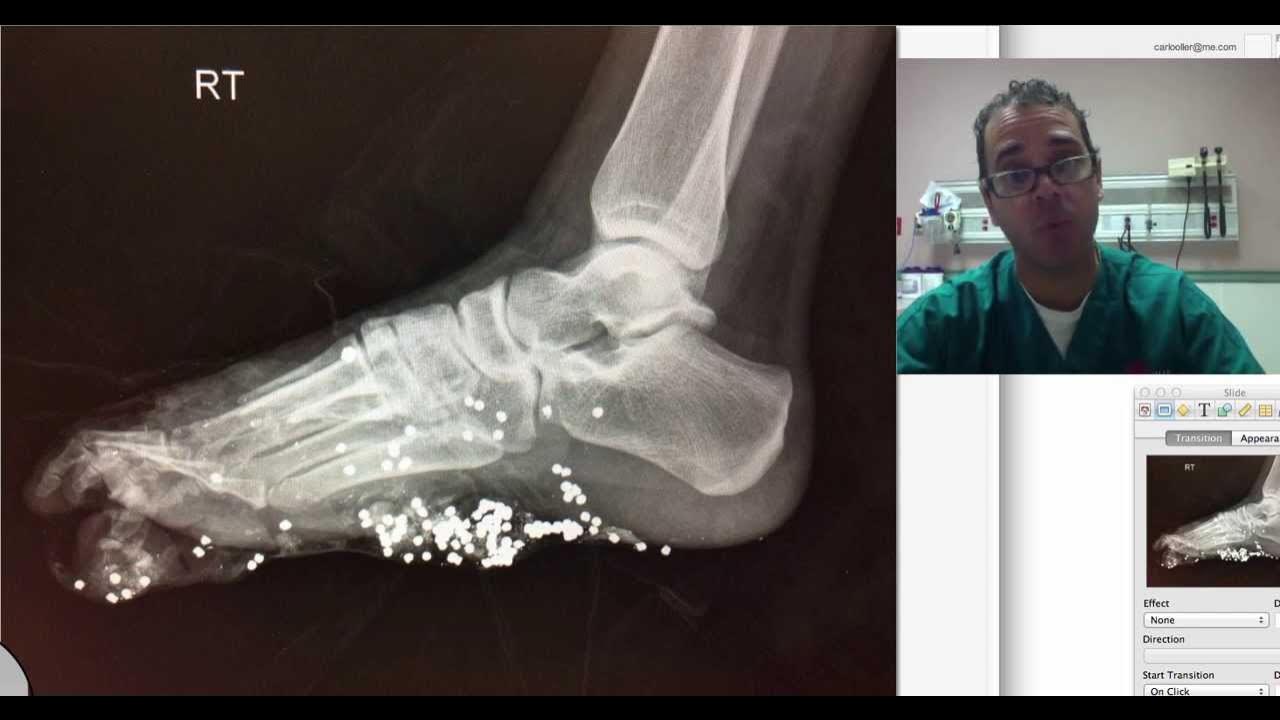

From www.youtube.com

foot xray potpourri YouTube Potpourri Xray A potpourri of xrays related to the foot and ankle.special discussion about jones vs pseudo jones. I am very happy with the comments and feedback i have been getting on this 'kind' of videos so i will. Here is another edition of my radiologic potpourri. Browse a wide range of potpourri products for your home, from scented dried flowers and. Potpourri Xray.